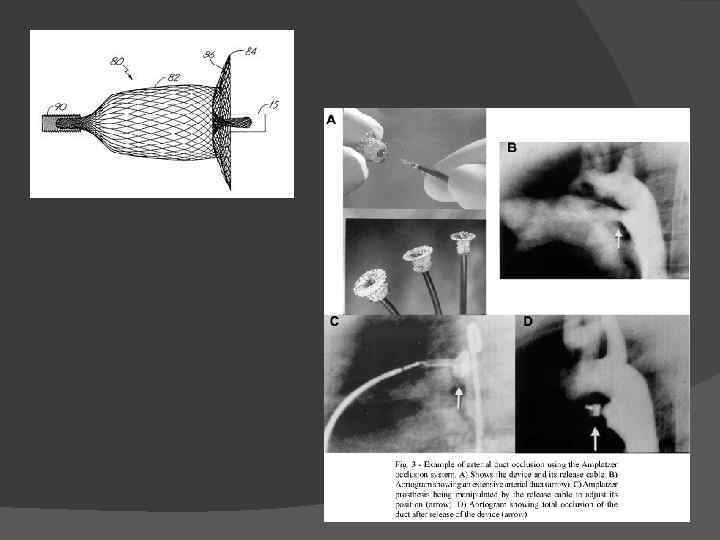

Эндоваскулярный доступ. Если диаметр боталлова протока менее 3 мм, то есть возможность его закрытия окклюдером без оперативного вмешательства. Окклюдер - своего рода "заклепка", которая доставляется к отверстию, которое нужно перекрыть и, благодаря своей конструкции закрывает это отверстие.